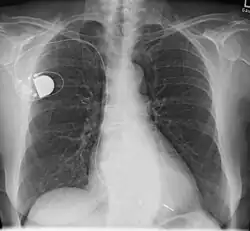

- Intrakardiale Stimulation durch Implantat: Der Herzschrittmacher wird oberhalb der rechten oder linken Brust unterhalb des Schlüsselbeines zumeist unter die Haut (subkutan) oder bei hageren Patienten unter den großen Brustmuskel (submuskulär) implantiert. Die Elektroden werden transvenös zum rechten Vorhof oder rechten Ventrikel geführt (beim biventrikulären Schrittmacher wird eine dritte Elektrode über den rechten Vorhof und den Koronarvenensinus zur Posterolateralwand des linken Ventrikels vorgeschoben). Diese Art der Implantation eines Herzschrittmachers ist die in der Praxis am häufigsten angewendete.